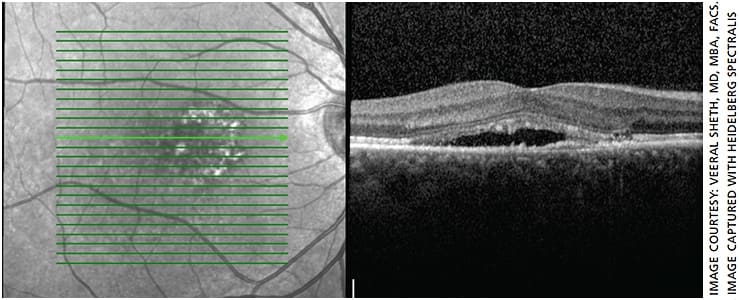

Similarly, Veeral Sheth, MD, MBA, FACS, partner & director of clinical trials, University Retina, with offices in the Chicago area, has used micropulse laser to treat patients with DME and CSCR (Figures 1-7). However, he notes, over the past decade he has used micropulse laser somewhat less for patients with DME and more for patients with CSCR. That’s because of the efficacy and safety profile of intravitreal injections for DME.

“The only quantification you have is when they follow up and you do an OCT and you see that there’s been improvement,” says Dr. Sheth.

One key to success is administering confluent treatment, notes Dr. Sheth. In traditional laser, he points out, you’re burning tissue and thus need to keep the spots fairly separated. With micropulse laser, “you’re able to actually cover an area more confluently and therefore treat more densely without the concern of burning or damaging tissue.”

“This dense or confluent treatment I think is critical,” he adds. “I think it’s something that physicians, especially early on with their use, don’t do, because they’re fearful, because it’s not traditionally how we do focal laser. The problem is, then you run the risk of not having optimal results. If you do a little bit more of this confluent type of treatment, you’re going to get better results.”